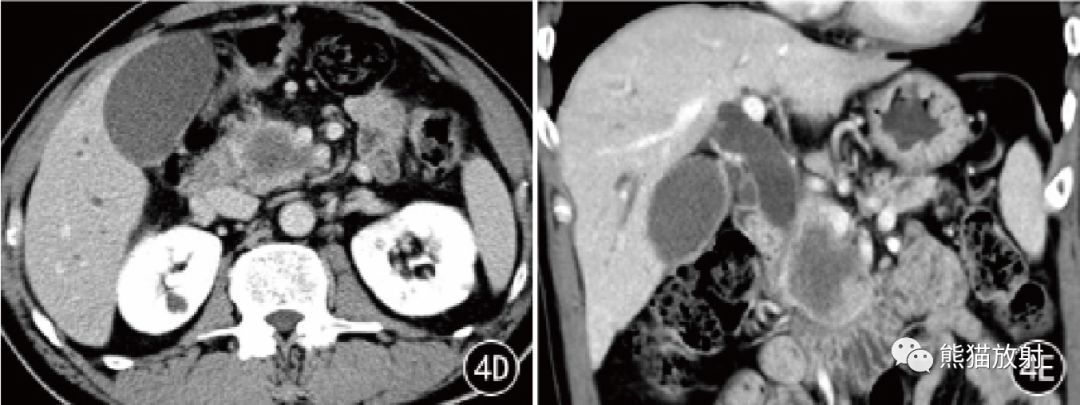

图4 男,65 岁。PDAC 胰头钩突部中分化导管腺癌。CT平扫显示略低密度肿块,增强扫描动脉期肿块轻度不均匀强化,门静脉期和延迟期渐进性强化不明显。冠状MPR示胰腺、尾部萎缩,胰管扩张,胆总管下端受侵、变窄,其上方胆内外胆管明显扩张。